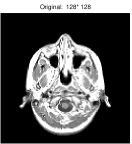

Besides the Shepp-Logan phantom image, we also tested Cameraman, Lena, Boat, Sailboat, as well as two brain images. In this experiment, we simply set and keep all other parameters unchanged. The original and the recovered images by TwIST and IADM are given in Figures 3 and 4, and detailed results including relative errors (RE), CPU time (Time), final objective function values (Obj), and the number of iterations (Iter) are presented in Table 2. It can be seen from Table 2 that IADM attained comparable or better image quality in less CPU seconds. For each test, IADM consumed more iterations while the CPU time is less because the per-iteration cost of IADM is much less than that of TwIST. Specifically, the per-iteration cost of IADM contains two matrix-vector multiplications and two FFTs, while TwIST needs to solve a TV denoising problem at each iteration. In addition, IADM always attained smaller function values. In summary, the comparison results indicate that IAMD performs favorably and can be competitive with the state-of-the-art algorithm TwIST.

| brain 1 | 52 | 14.01% | 34.25s | 4.7831e+002 | 208 | 13.64% | 20.41s | 4.5478e+002 | |

| brain 2 | 48 | 9.59% | 90.22s | 1.6397e+003 | 176 | 9.45% | 61.67s | 1.5665e+003 | |